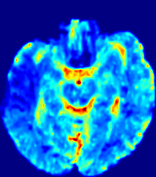

TimeSlice(i)(ii)(iii)(iv)(v)(vi)Refer to caption00777141414212121282828353535Refer to caption(a)(b)Refer to captionRefer to captionRefer to captionRefer to captionRefer to captionRefer to captionRefer to captionRefer to captionRefer to captionRefer to captionRefer to captionRefer to captionRefer to captionRefer to captionRefer to captionRefer to captionRefer to captionRefer to caption(a)(b)Refer to captionRefer to captionRefer to captionRefer to captionRefer to captionRefer to captionRefer to captionRefer to captionRefer to captionRefer to captionRefer to captionRefer to captionRefer to captionRefer to captionRefer to captionRefer to captionRefer to captionRefer to caption(a)(b)Refer to captionRefer to captionRefer to captionRefer to captionRefer to captionRefer to captionRefer to captionRefer to captionRefer to captionRefer to captionRefer to captionRefer to captionRefer to captionRefer to captionRefer to captionRefer to captionRefer to captionRefer to caption(a)(b)Refer to captionRefer to captionRefer to captionRefer to captionRefer to captionRefer to captionRefer to captionRefer to captionRefer to captionRefer to captionRefer to captionRefer to captionRefer to captionRefer to captionRefer to captionRefer to captionRefer to captionRefer to caption(a)(b)Refer to captionRefer to captionRefer to captionRefer to captionRefer to captionRefer to captionRefer to captionRefer to captionRefer to captionRefer to captionRefer to captionRefer to captionRefer to captionRefer to captionRefer to captionRefer to captionRefer to captionRefer to caption(a)(b)Refer to captionRefer to captionRefer to captionRefer to captionRefer to captionRefer to captionRefer to captionRefer to captionRefer to captionRefer to captionRefer to captionRefer to captionRefer to captionRefer to captionRefer to captionRefer to captionRefer to captionRefer to caption

Figure 5: Predicted concentration time series for the same patient shown in Fig. 3, where (i)-(vi) correspond to slices #1-6 respectively. Each grouped row displays (a) the measured concentration image sequences and (b) the predicted concentrations at corresponding time points.

3.2 Predicted CA Concentration

To better illustrate the prediction accuracy, and therefore the estimation accuracy of 𝐕𝐕{\bf V} and D𝐷{D}, of PIANO, we provide the corresponding predicted time-series of CA concentration images in Fig. 5 and Fig. 6 for the same patients in Fig. 3 and Fig. 4, respectively. We see that PIANO is capable of predicting the CA concentration given their initial state, indicating its ability to successfully capture 𝐕𝐕{\bf V} and D𝐷{D}. Note that although the concentration values for these two patients differ considerably, caused by the different total volume of injected CA, PIANO is still able to provide plausible estimates.